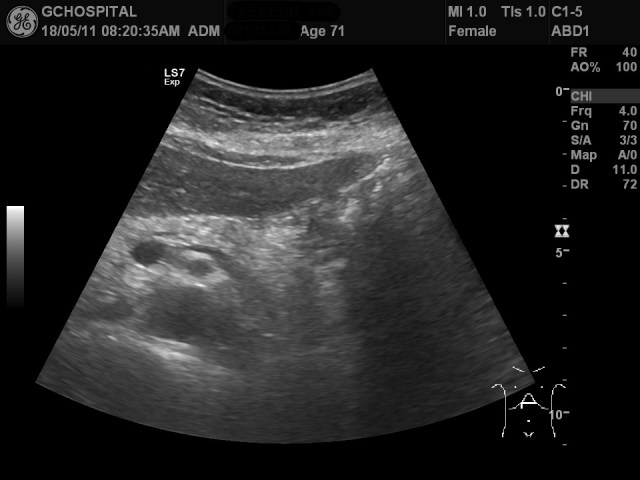

올해에도 췌장낭종의 추적관찰을 위해 내원하셔서 췌장부위를 촬영한 게 위의 영상입니다. 그런데, 영상에서 췌장낭종이 확인되지 않고 있습니다.

뿐만 아니라 췌장의 꼬리부위에 흐릿하게 저에코음영이 있는것처럼 보이기도 합니다. 과연, 췌장에 저에코의 종괴나 췌장염과 같은 병변을 의심해야 하는걸까요?